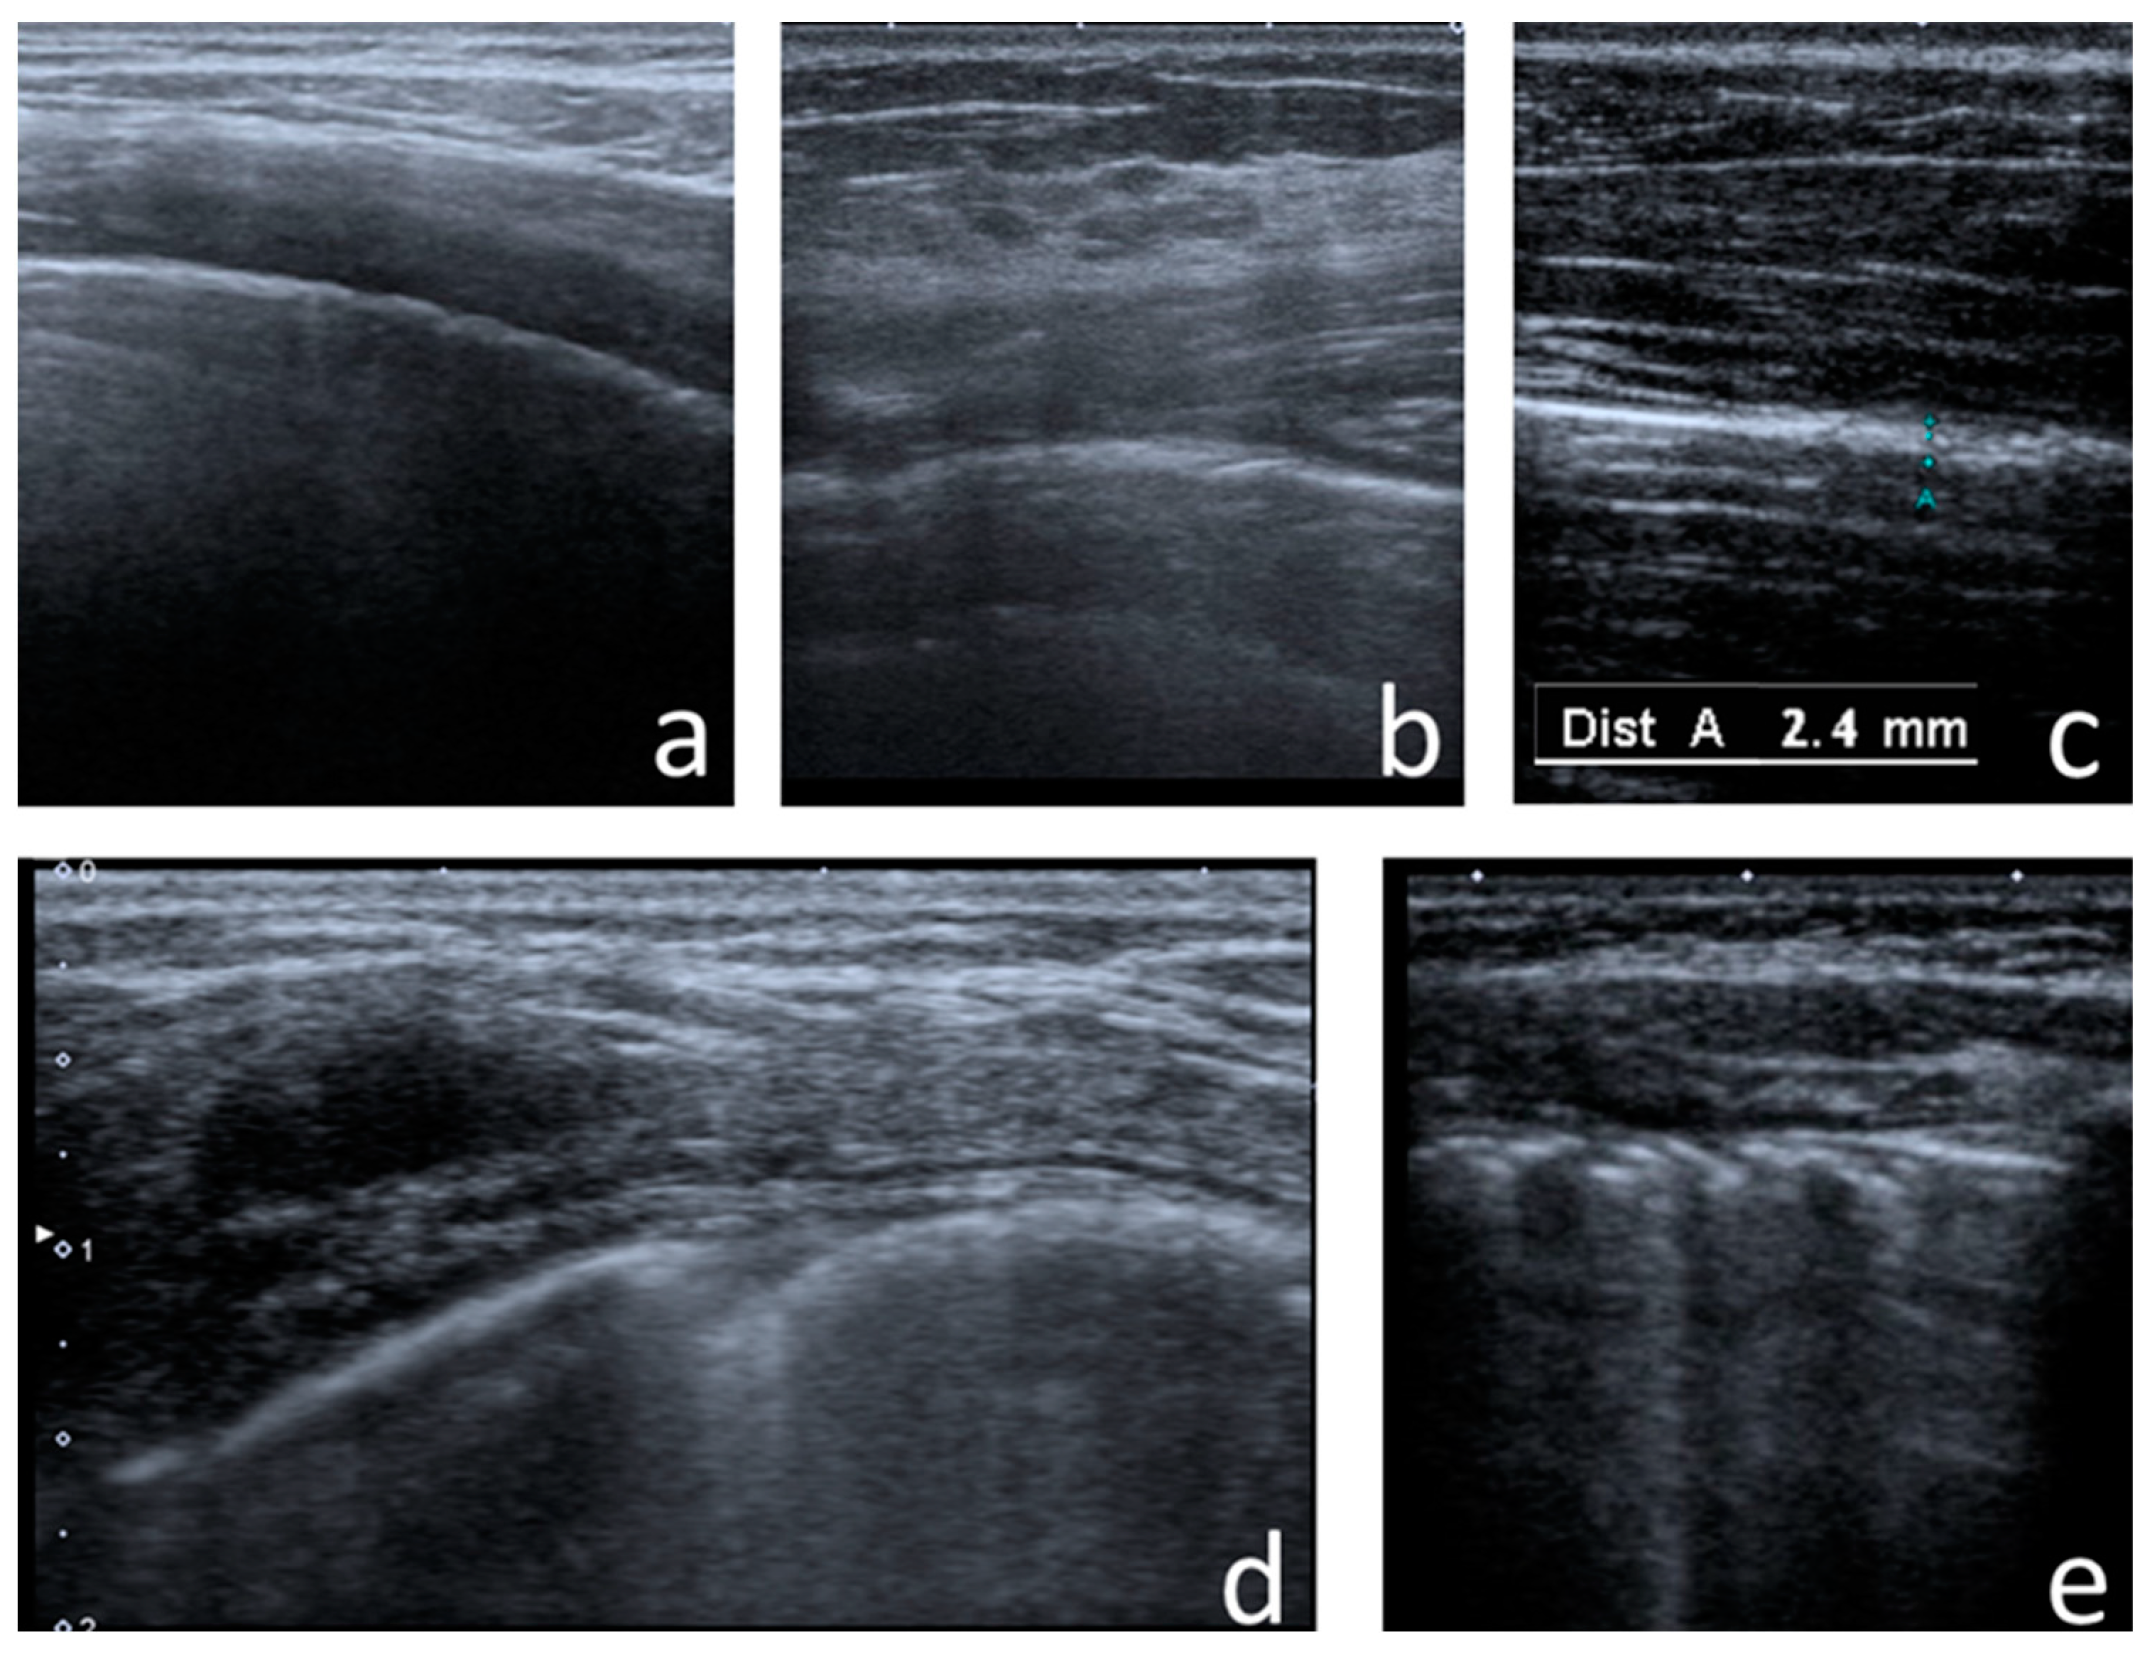

- Consolidations—hypoechoic, tissue-like areas: (a) small (≤10 mm) (Figure 6), and (b) major (>10 mm) (Figure 7); usually, major consolidations have the following associated features: the loss of pleural line echogenicity over the area of consolidation, absence of A-lines, presence of dynamic or static air bronchogram/air trapping and vascular pattern (in CD option) within the area, C-lines below the area, B-lines surrounding it [17,31];